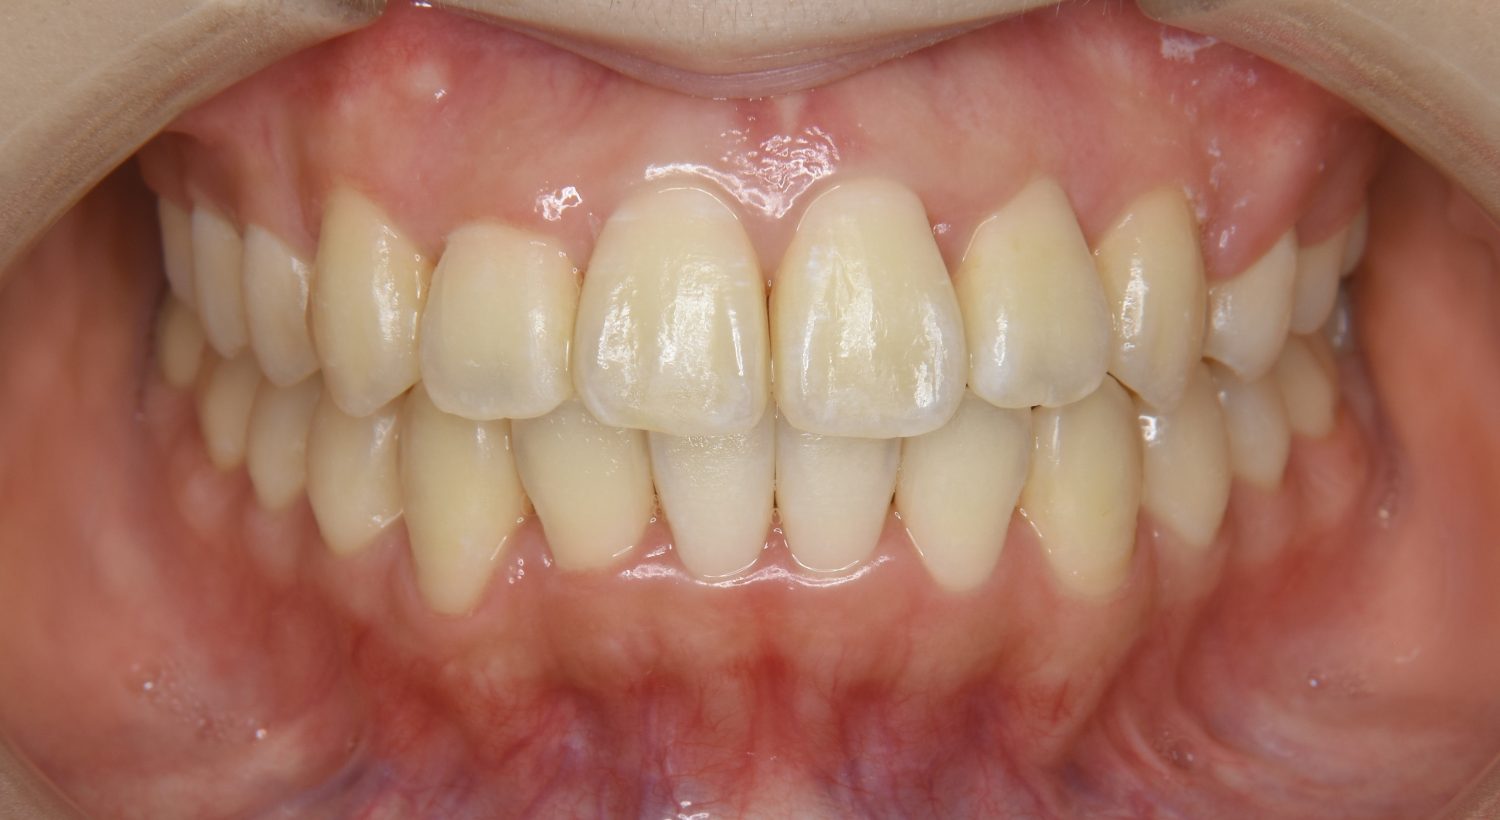

上顎前突の症例紹介①

Before

After

主訴

上の歯が出ている。歯並び全体が気になる。

治療内容

上顎両側第一小臼歯を抜歯し、上下ラビアルブラケット(唇側装置)に矯正用アンカースクリューを併用し治療を行いました。

上顎前歯の前突により口元の突出が認められました。上の左右の第一小臼歯を抜歯し上顎前歯を後退させることで口元の突出感は改善し、咬合も良好な状態となりました。